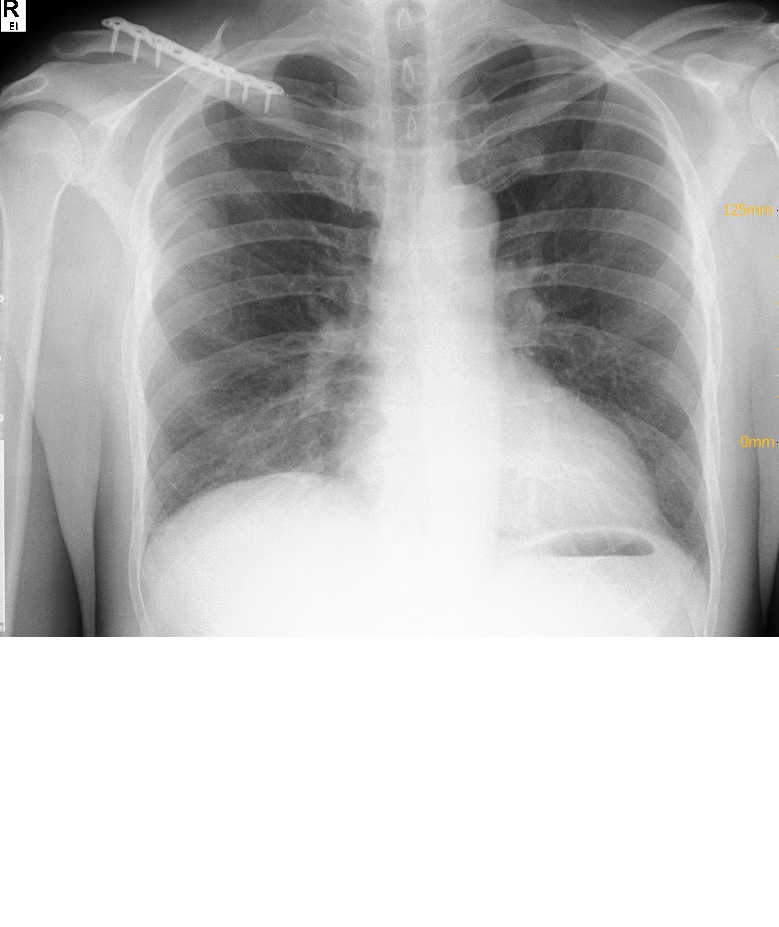

Nächten Tag morgens dann Notaufnahme, röntgen mit Gewicht. Diagnose Rockwood 2. Ansage: 4 Wochen Gilrichst, in 2 Wochen nochmal beim Örtlichen Orthopäden zur Nachsorge vorstellig werden. Soweit so gut.

Dann, hatte ich eine Woche Später noch die Idee zusätzlich zum Bericht der Notaufnahme noch den des Radiologen anzufordern, hier stand dann: Tossy 3. Danach natürlich erstmal Kopfkino, könnte Tossy 3 nicht operiert werden? Was ist der Unterschied? Warum sagen dier in der Notaufnahme was anderes?